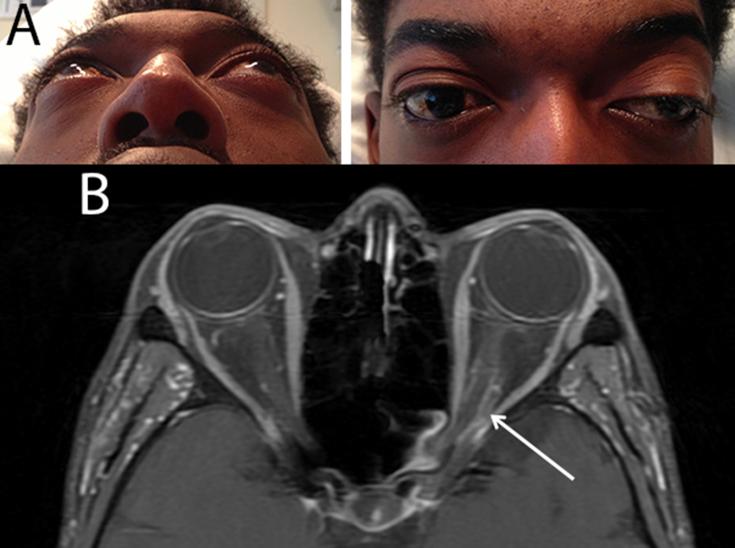

27 year-old renal transplant recipient presented with a two-week history of headache, binocular diplopia and proptosis of the left eye. Endonasal biopsy on hospital day 3 confirmed the diagnosis of rhino-orbital invasive involving the left orbital apex.In addition to systemic antifungal treatment and cessation of immunosuppression, retrobulbar amphotericin B injections (3.5 mg/1 ml) combined with endoscopic local debridement were initiated when the patient developed progressive visual loss. Retrobulbar injections were administered on hospital days 8, 10, 14, 17, and 20. Endoscopic debridement occurred on hospital days 10 and 16.After the fifth retrobulbar amphotericin B injection, the patient developed acute orbital compartment syndrome with intraocular pressures ranging from 47 to 86 mmHg and vision declined to 20/200, requiring emergent lateral canthotomy and superior and inferior cantholysis. Close observation without further intervention resulted in return of vision to 20/20 and normalization of intraocular pressure.

Retrobulbar amphotericin B in combination with local debridement may be considered an alternative to exenteration for invasive aspergillosis secondary to reversible immunosuppression. To the authors' knowledge, orbital compartment syndrome secondary to retrobulbar amphotericin B administration has not previously been reported. Patients should be counseled on the risk of severe local inflammation due to amphotericin B. More research is needed to establish the most appropriate dosing, frequency, and duration of retrobulbar amphotericin B injections in the treatment of life-threatening infections.